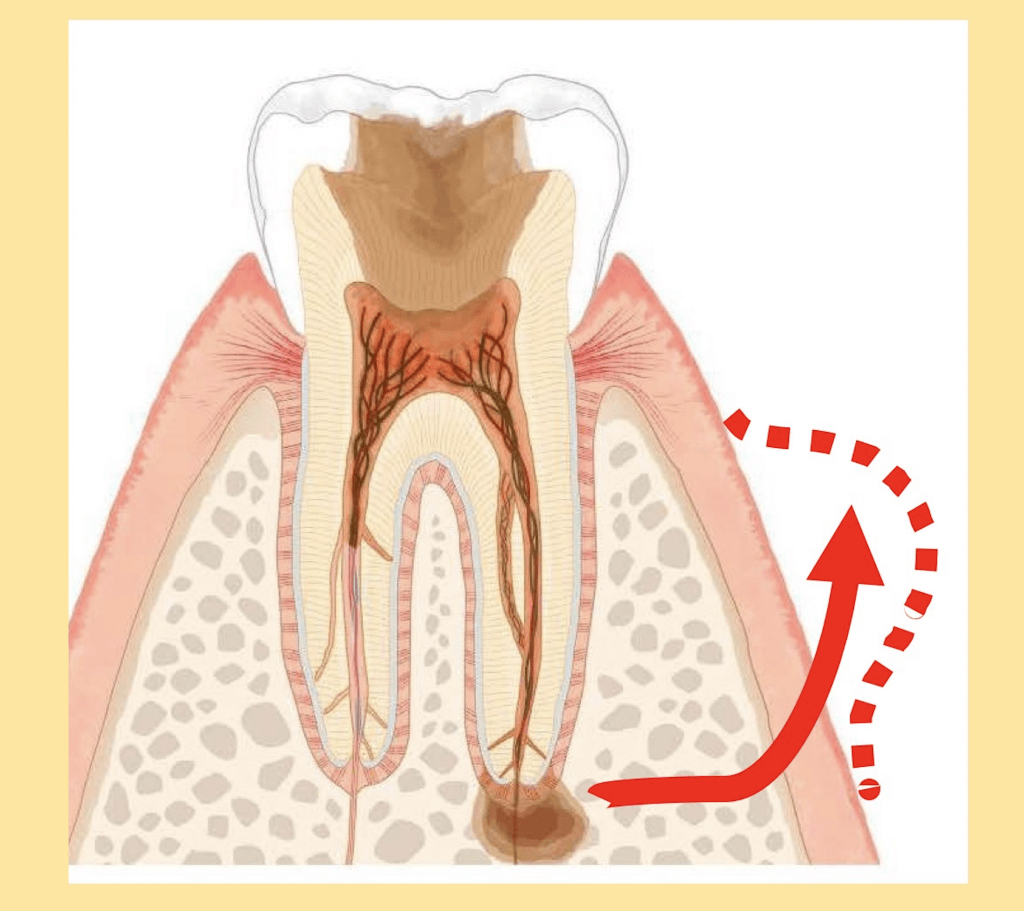

根尖性周囲炎によるもの

根の先に膿がたまると膿は骨を溶かしながら外へ飛び出ていきます。そのため歯ぐきにぷくっとしたものができることがあります。このぷくっとしたものを歯ぐきが腫れたと感じることがあります。